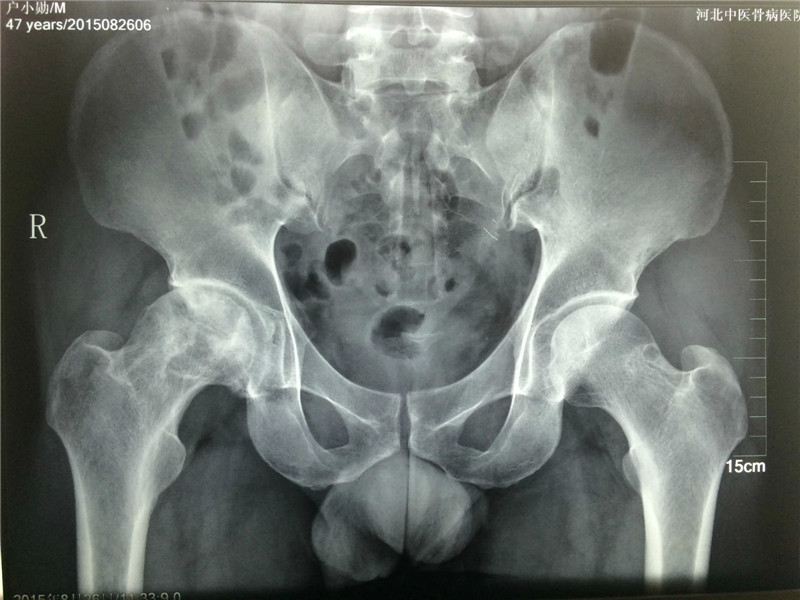

河北户先生股骨头坏死治疗病例

河北户先生自己也记不清楚是什么时候出现髋关节疼痛的,反正有一段时间了。因为疼痛加重、活动受限,在医院诊治,得知是股骨头坏死疾病,后辗转到我院治疗。

入院时:股骨头边缘不光滑、边缘有塌陷、骨质破坏严重